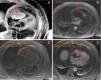

A 65-year-old man with a history of thrombocytopenia currently under investigation, hypertension and diabetes, was hospitalized with decompensated heart failure, mainly right-sided. Transthoracic echocardiography (Figure 1) showed preserved biventricular function and a relatively immobile heterogeneous mass, 2.5 cm in diameter, in the right ventricle (RV), that was difficult to characterize because of poor echocardiographic image quality and patient discomfort. Transesophageal echocardiography (Figure 2), interrupted due to dyspnea, revealed that the mass was adhering to the lateral wall of the right atrium (RA) and extended to the tricuspid valve (causing obstruction), the RV and the pericardium. Provisional diagnoses were thrombus or tumor, its heterogeneous appearance and infiltrative nature suggesting the latter. Thoracic-abdominal-pelvic computed tomography was accordingly performed to investigate a possible occult tumor, but this showed no alterations other than bilateral pleural effusion and a large cardiac mass occupying the right chambers and obliterating the external RA wall. Cardiac magnetic resonance imaging (Figure 3) showed a neoplasm adhering to the lateral RA wall and protruding into the RV, suggestive of an intracardiac tumor.

Cardiac magnetic resonance imaging showing an intracavitary mass (arrow) adhering to the lateral wall of the right atrium, measuring 56 mm×87 mm×47 mm, protruding above the atrial appendage, through the tricuspid valve, into the right ventricle and below the atrial wall. (A) Relatively homogenous high signal intensity in T2 and equal signal intensity compared to the myocardium in T1 (C and D); predominantly central enhancement throughout the perfusion study (B), with areas of peripheral hypoperfusion. Slight pericardial effusion can be seen.